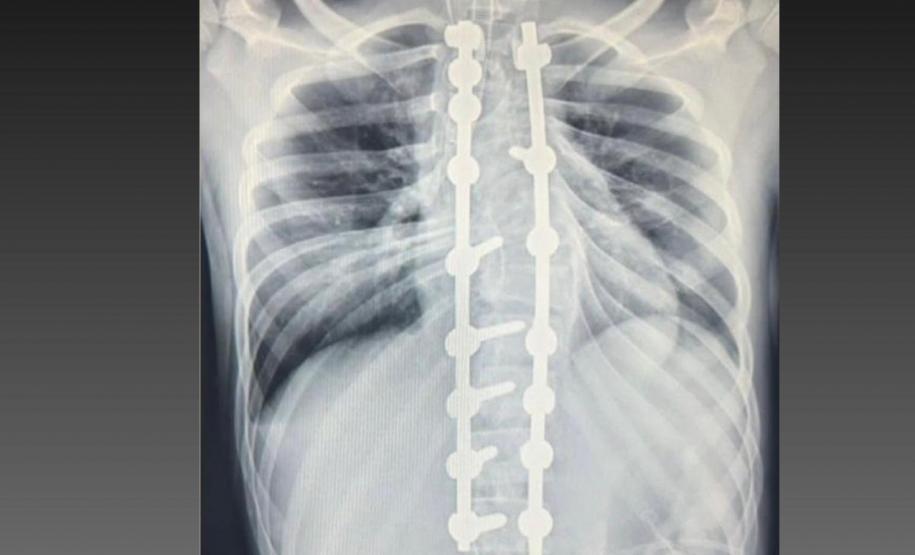

Laura era portadora de escoliose e, em agosto de 2025, realizou a cirurgia de correção da coluna, o que lhe permitirá ter uma vida normal de agora em diante. Moradora de Bom Sucesso do Sul, região Oeste do Paraná, é acostumada a andar a cavalo, mas com o problema na coluna a prática estava longe de ser prazerosa.

A cirurgia ocorreu no dia 28 de julho e uma segunda etapa em quatro de agosto. Desde então, Joyce viu a sua vida mudar. “Nasci com a escoliose e tinha muita dificuldade e limitações para caminhar e perda de movimento. Havia dias em que eu não levantava da cama. Quando saia de casa recebia olhares de julgamento das pessoas, que era o que mais me incomodava. Depois da cirurgia, posso dizer que eu tenho uma nova vida. Eu venci a batalha”, relatou.